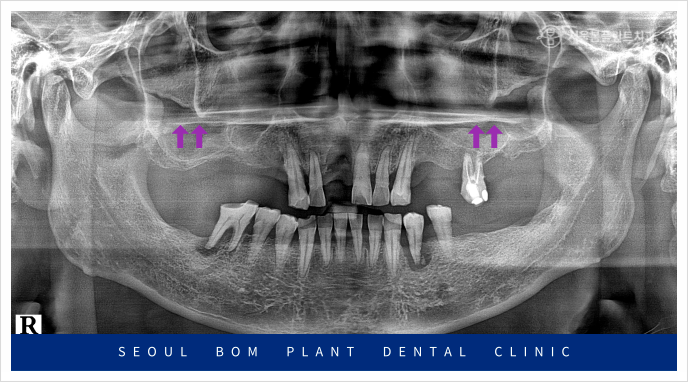

오늘은 위턱 앞니의 임플란트 탈락으로

송파구치과 서울봄플란트치과를

내원해 주신 사례를

소개해 드리겠습니다.

환자분께서는 50대 초반의

남성분으로 타 치과에서 했던

오른쪽 위턱 첫 번째 앞니(#11)의

임플란트가 빠져 상담을 위해

내원해 주셨는데요.

앞니는 원래도 잇몸뼈가 얇은 데다가

환자분께서는 임플란트 주위염으로 인해

잔존 잇몸뼈가 약해져

기존 임플란트가 탈락한 상황이었는데요.

정밀한 검사를 위해

파노라마 사진을 촬영해 보았더니

잇몸뼈 소실로 많이 약해져 있는 상태라

다시 임플란트를 식립하기에는

무리가 있었습니다.

위턱 오른쪽 앞니(#11)의 경우

환자분과 충분한 상담을 통해

양옆의 치아를 이용한

브릿지 보철물을

진행하기로 계획하였는데요.

기존 임플란트가 빠지고

잇몸뼈가 소실이 심한 상태라

잇몸뼈가 어느 정도 찰 때까지

충분한 시간을 가지고

진행하기로 하였으며,

빨간색 동그라미 표시의

위턱 왼쪽 첫 번째 큰 어금니(#26)와

아래턱 왼쪽 작은 어금니(#34,35)

아래턱 오른쪽 첫 번째 큰 어금니(#46)가

뿌리 끝 염증과 함께 동요도도 심한 상태라

발치가 불가피한 상황이었습니다.